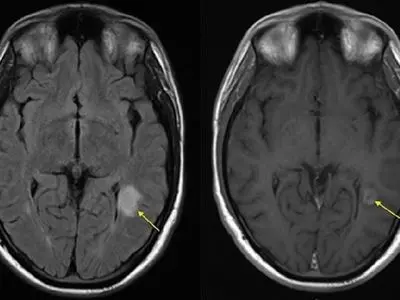

• سیستم عصبی ما یک شاهکار مهندسی است؛ شبکه‌ای هوشمند که فرمان‌های مغز را در کسری از ثانیه به تمام بدن مخابره می‌کند. اما تصور کنید در این شبکه پیچیده، برخی از مسیرهای ارتباطی دچار اختلال یا اتصال کوتاه شوند. این دقیقا اتفاقی است که با تشکیل پلاک‌های مغزی و نخاعی رخ می‌دهد. این ضایعات می‌توانند عملکرد طبیعی بدن را مختل و علائمی ایجاد کنند که کیفیت زندگی را تحت تاثیر قرار می‌دهد. در ادامه به این موضوع می‌پردازیم که پلاک مغزی و نخاعی چیست و چگونه می‌توان آن را مدیریت کرد.